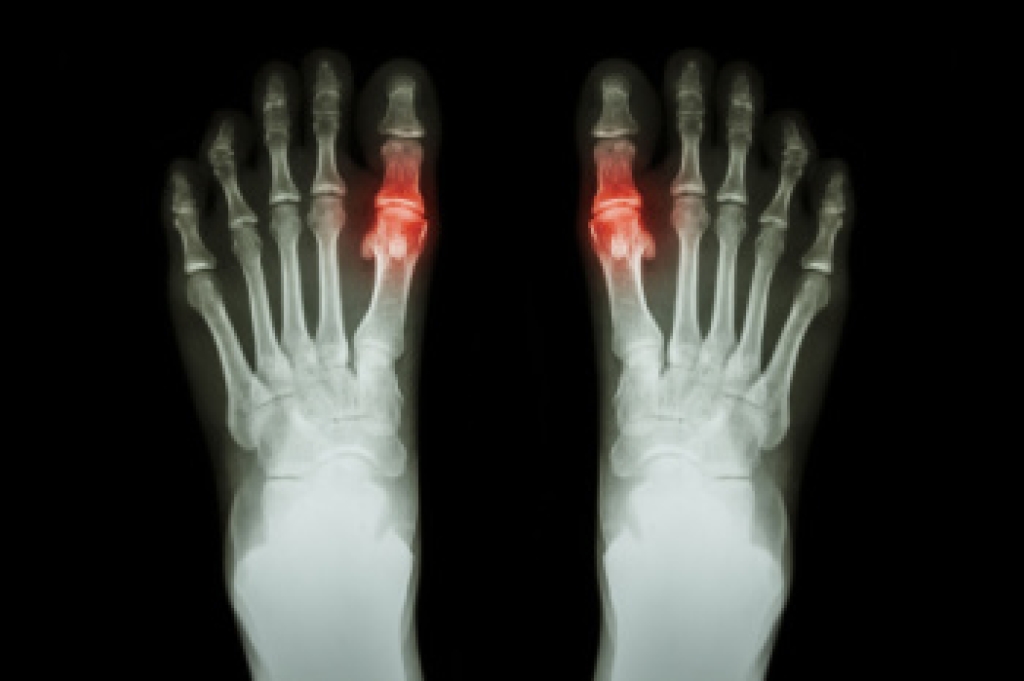

Gout in Teenagers

Gout is a crystalline inflammatory arthritis caused by the buildup of uric acid crystals within the joints. Although it is more common in adults, the prevalence of gout among teenagers is increasing due to obesity, poor diet, and certain medical conditions. It often affects the big toe, causing sudden joint pain, redness, swelling, and warmth. Repeated flare-ups may lead to joint deformities and, in severe cases, may contribute to kidney dysfunction and other systemic concerns. Risk factors include family history, metabolic disorders, and high consumption of sugary beverages or processed foods. A podiatrist can diagnose gout, manage painful symptoms, and coordinate comprehensive care. If your teenager has symptoms of gout, it is suggested that you consult a podiatrist who can provide an accurate diagnosis and relief options.

What Is Gout?

Gout is a type of arthritis caused by a buildup of uric acid in the bloodstream. It often develops in the foot, especially the big toe area, although it can manifest in other parts of the body as well. Gout can make walking and standing very painful and is especially common in diabetics and the obese.

Gout can easily be identified by redness and inflammation of the big toe and the surrounding areas of the foot. Other symptoms include extreme fatigue, joint pain, and running high fevers. Sometimes corticosteroid drugs can be prescribed to treat gout, but the best way to combat this disease is to get more exercise and eat a better diet.